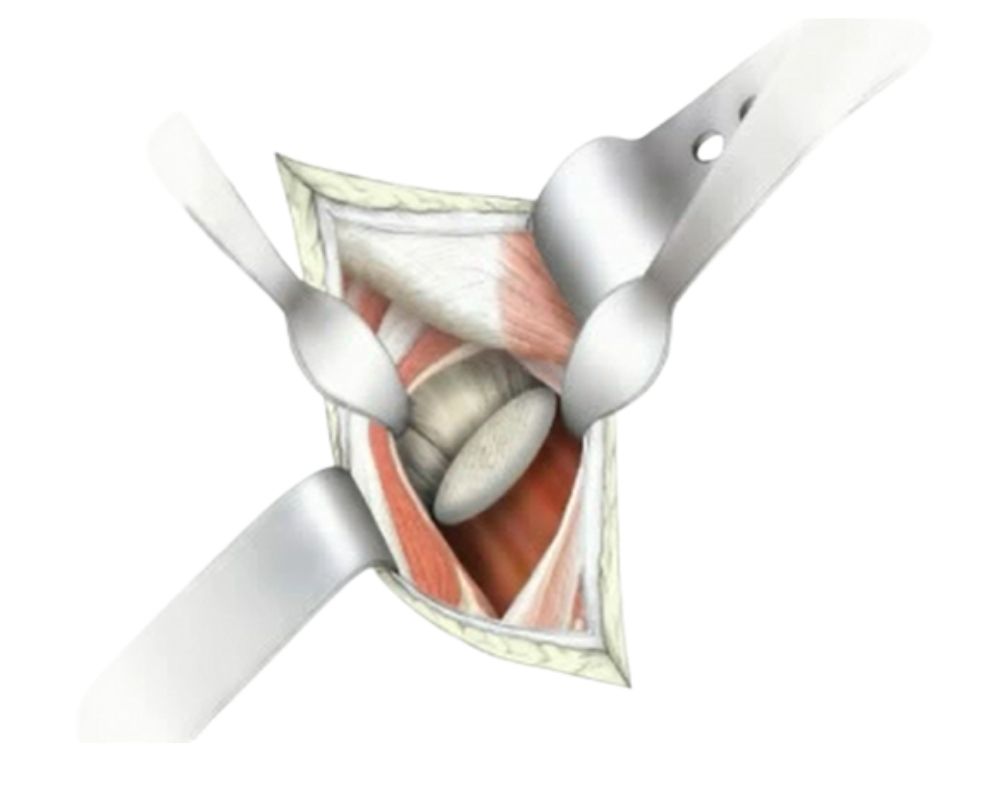

Accesso MIPSA e protocollo ERAS

Da quasi vent’anni utilizzo una via d’accesso mininvasiva denominata MIPSA (Minimally Invasive Piriformis Sparing Surgery Approach) che ha reso il percorso riabilitativo dopo un intervento di protesi d’anca il più veloce ma anche il più sicuro possibile.

Pubblicata nel 2005, questa tecnica, che si avvale di una via d’accesso di dimensioni ridotte (8-10 cm), si basa sulla preservazione del muscolo piriforme e del quadrato femorale. Questo approccio è minimamente invasivo sia sulle parti molli (muscoli e tendini) che sulla componente ossea, con notevole riduzione del sanguinamento intra- e post-operatorio e molti vantaggi sul recupero funzionale.

Nella mia esperienza chirurgica, la MIPSA dà risultati equivalenti alla via d’accesso anteriore, ma con maggior possibilità di gestire le possibili complicanze. Peraltro, preservando il muscolo piriforme, che svolge una funzione propriocettiva, il paziente sente l’anca più come sua.